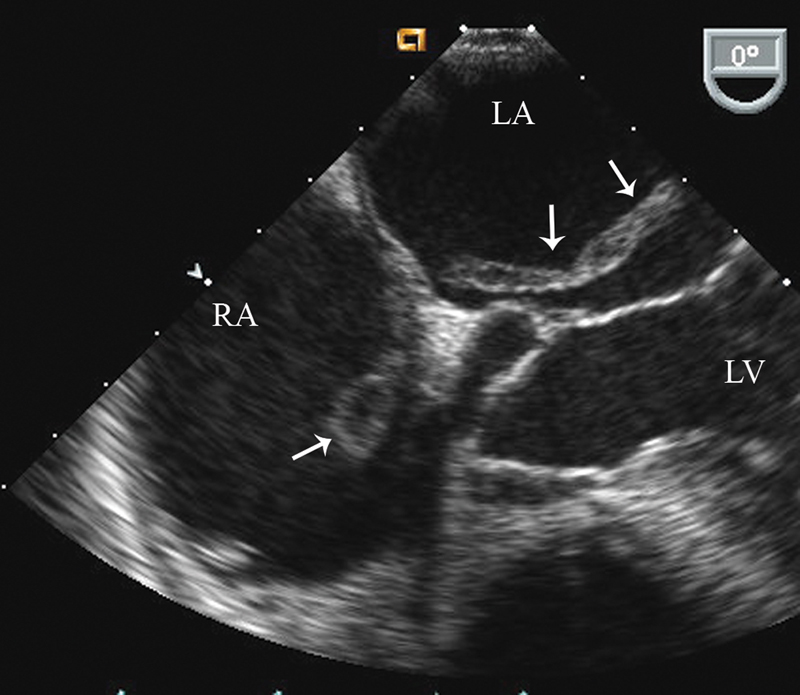

فحوصات تشخيصية لبعض امراض القلب والشرايين التاجية